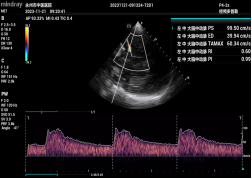

重症医学科医生为动脉瘤患者行TCCD检查

脑血流评估 ONSD测量